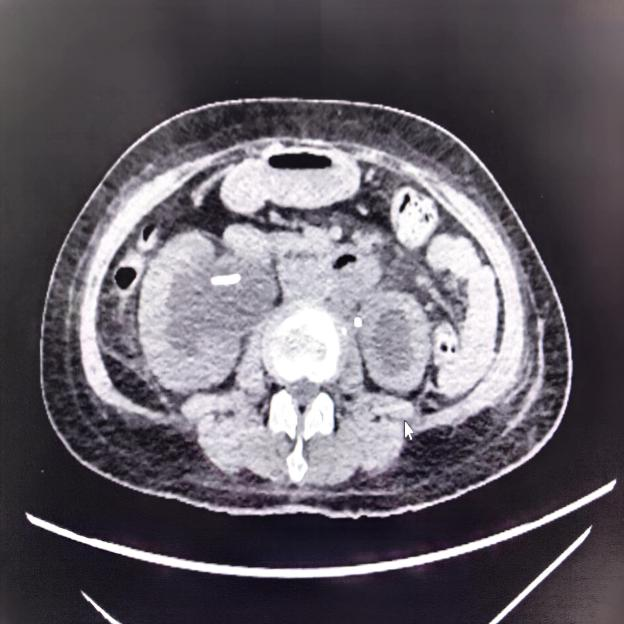

术后复查影像显示患者肾积水明显减轻,尿液引流通畅

术后,阳女士的肾功能得到显著改善,在夹闭肾造瘘管的情况下,肌酐值从术前的168.7umol/L降至正常范围。后续影像复查确认,尿液已能经由温控支架架构的“新通道”顺畅流入膀胱。最终,阳女士在出院前成功拔除了困扰她已久的肾造瘘管。